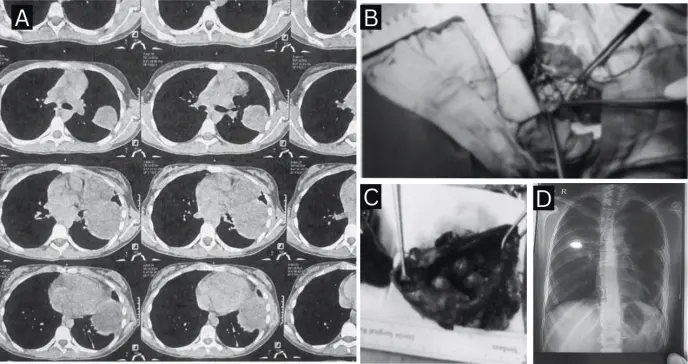

Posteriormente, una tomografía computarizada (TC) de tórax con contraste confirmó la existencia de dos masas independientes: una en el mediastino anterior y otra en el lóbulo superior izquierdo del pulmón, ambas con características sugestivas de lesiones quísticas o tumorales.

El estudio anatomopatológico confirmó el diagnóstico de un teratoma quístico maduro mediastínico, compuesto por tejido epitelial escamoso, glándulas sebáceas, folículos pilosos, epitelio gastrointestinal y músculo liso.

Asimismo, se identificó un quiste broncogénico infectado intrapulmonar, revestido por epitelio respiratorio ciliado, con evidencia de hemorragia alveolar y formación de abscesos.

La intervención permitió la resección completa de un teratoma mediastínico de 7.5 × 4.5 cm y de un quiste broncogénico de 11.5 × 5.5 cm. La resolución quirúrgica fue definitiva, sin complicaciones ni lesiones residuales, y con desaparición total de los síntomas respiratorios.